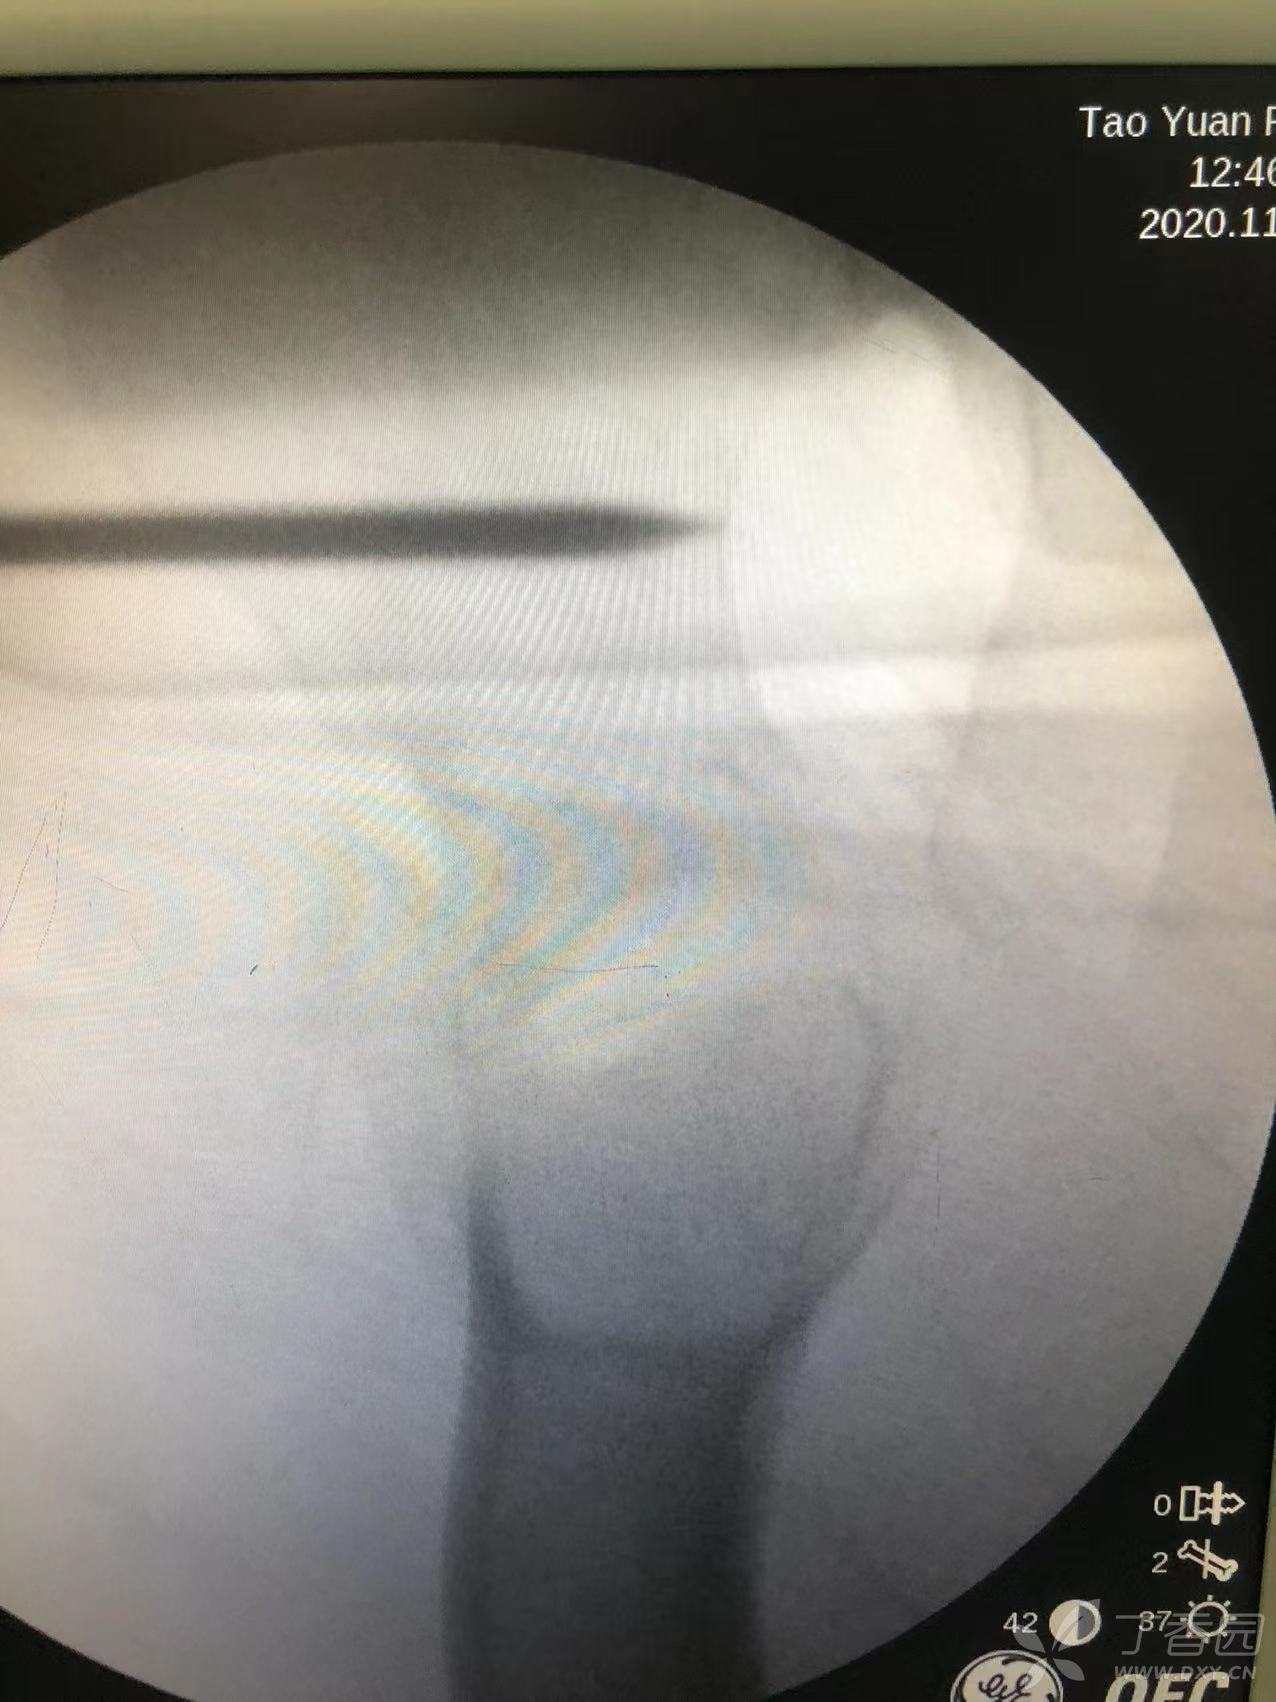

患者置于牵引床上,正位在股骨颈偏下方处垂直打入一枚4.0斯氏针。

通过这枚斯氏针控制近端旋转。